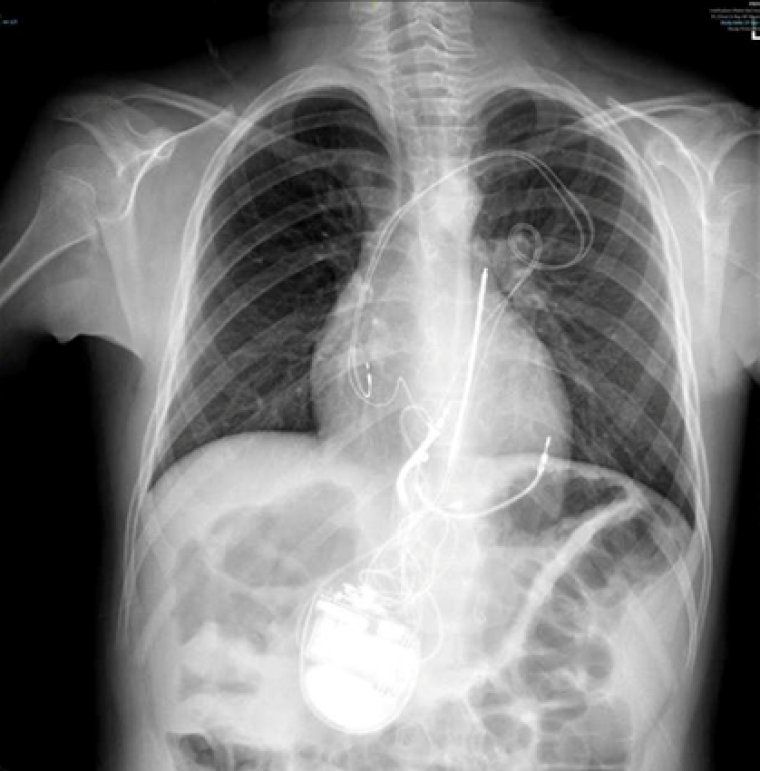

During the procedure, VF was induced with burst pacing after administering Isoprenaline. Despite adjusting the sensing threshold to 0.6mV, the ICD could not effectively detect VF, and a successful shock required changing the configuration from coil to can. Recognizing the device's inability to safely provide effective therapy during VF, a multi-disciplinary team meeting approved a "hybrid approach". The patient underwent ICD system revision, with the generator changed and left in an abdominal position. A transvenous atrial and ventricular pace-sense lead was inserted and tunnelled subcutaneously to the abdominal pocket, and an ICD shock coil was positioned subcutaneously anteriorly at the left parasternal site, with the shock set between the prior epicardial coil and the new subcutaneous coil (Image 3, 4a,b).

CC Vol 10 Picture3_Clinical case.png

CC Vol 10 Picture4A_Clinical case.png

CC Vol 10 Picture4B_Clinical case.png